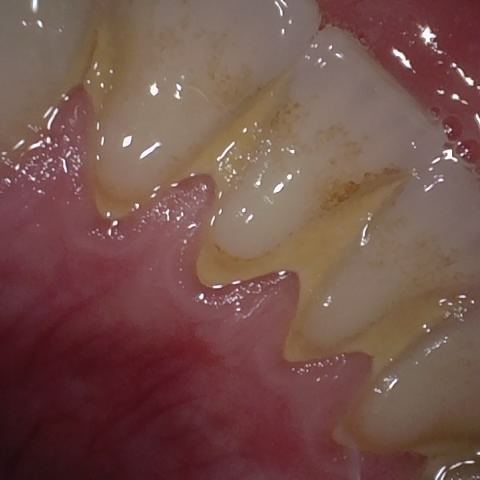

Image 789 / 1527

NHD39455

Annotated as "Good"

Original Image Rendering Image